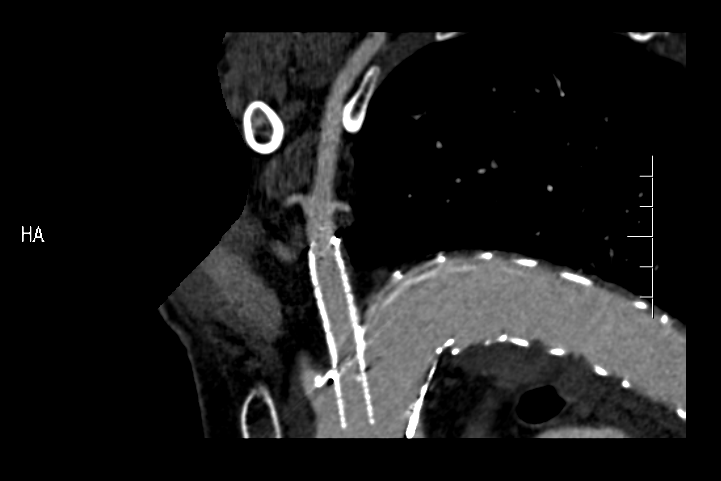

▲ 实例:术中造影可见破口

▲ 单纯覆膜支架植入覆盖破口